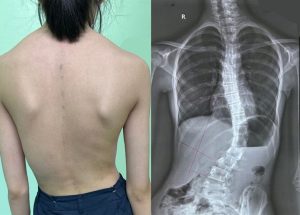

Cong vẹo cột sống là một tình trạng biến dạng ba chiều của cột sống, không chỉ đơn thuần là “tư thế xấu”. Thay vì thẳng, cột sống bị cong sang một bên theo hình chữ “C” hoặc chữ “S”, và đồng thời các đốt sống cũng bị xoay.

Bệnh lý này thường phát triển trong giai đoạn dậy thì (10-15 tuổi), khi trẻ đang trong giai đoạn tăng trưởng nhanh. Việc phát hiện sớm và can thiệp kịp thời là yếu tố quan trọng nhất để ngăn chặn đường cong tiến triển và tránh các biến chứng lâu dài.